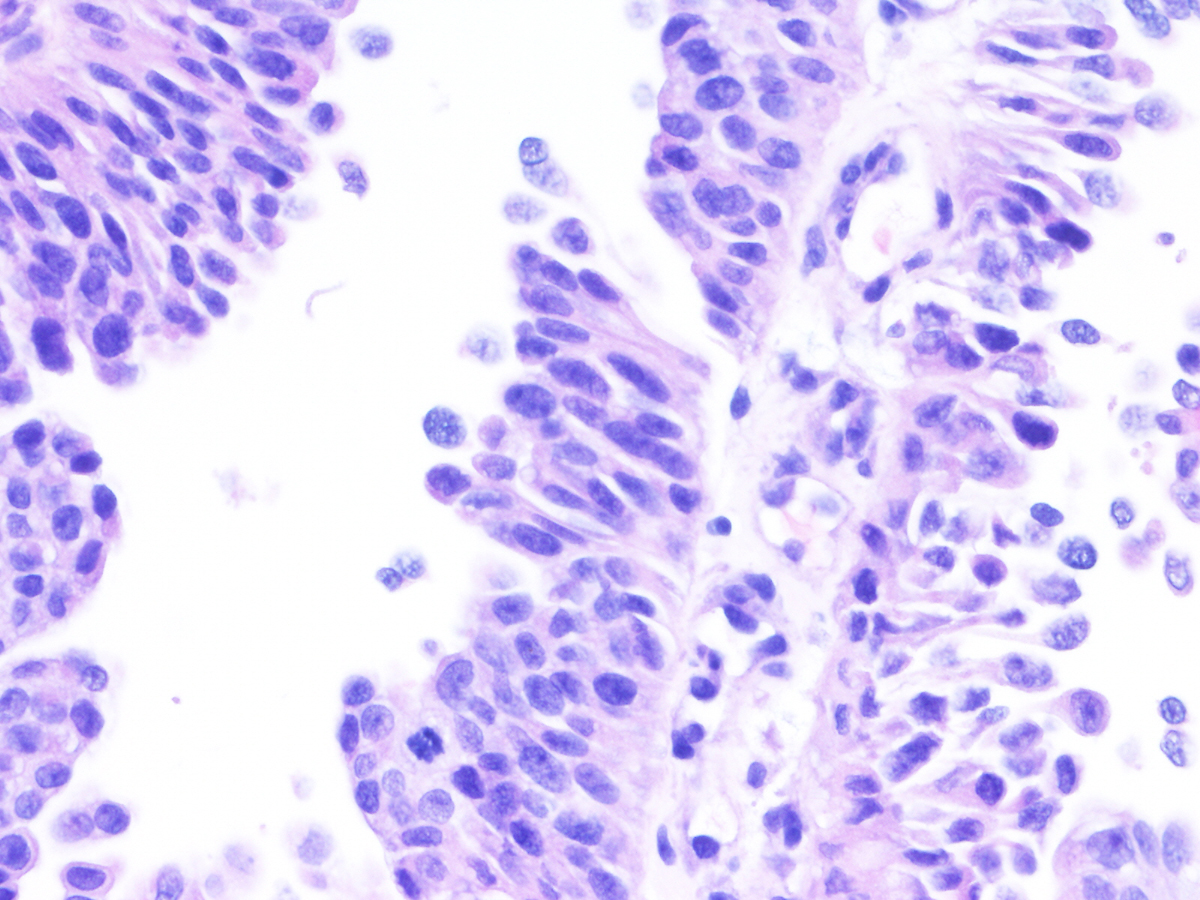

Bladder Papillary Lesions

Case ID: 543